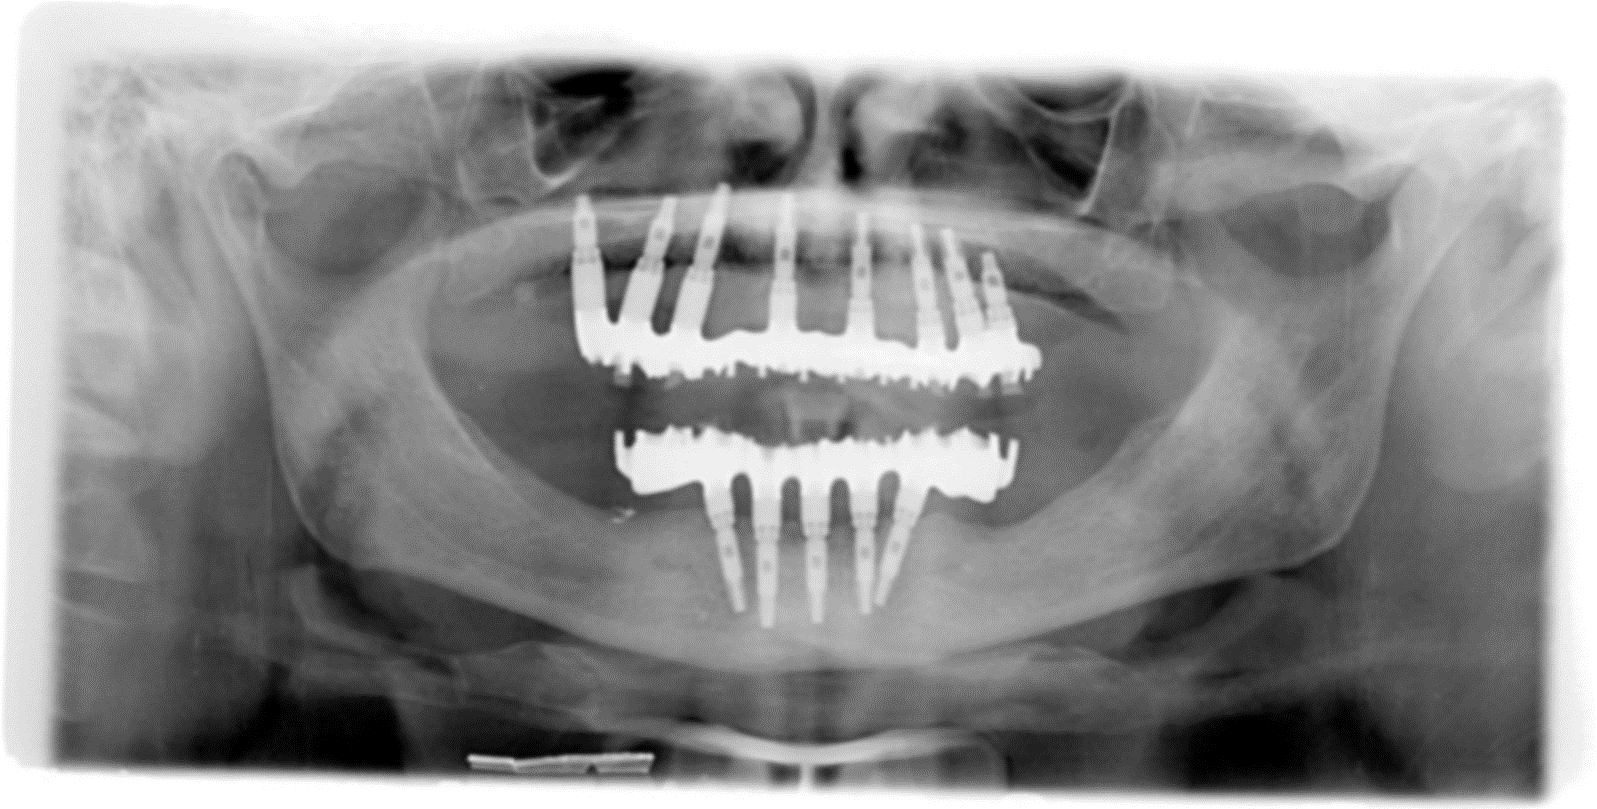

L'implantologia diventa quindi in questo ambito riabilitativo l'alternativa per eccellenza, in quanto permette il ripristino totale della funzione masticatoria con denti fissi. Tale protesi completa con impianti, è conosciuta come "Toronto Branemark Bridge" e prevede secondo il protocollo svedese originale, l'inserimento di un numero adeguato di impianti nelle arcate ed in posizioni idonee tali da sostenere meccanicamente la successiva protesi fissa ed il relativo carico masticatorio (almeno 6 nell’arcata superiore e 5 nell'inferiore). Relativamente al numero di impianti che sono necessari per soddisfare le condizioni meccaniche utili ad applicare su di essi una protesi fissa, negli ultimi anni è venuta a mancare la consueta chiarezza. Come detto poco sopra il protocollo svedese originale recita testualmente:

nell’arcata superiore “almeno sei impianti nell’area della premaxilla, ovvero l’area ossea compresa tra i seni mascellari da entrambi i lati”

nell’arcata inferiore “cinque impianti nella regione del mento, entro i limiti anatomici determinati dal nervo mentoniero”.

Queste sono le indicazioni vorremo dire “archetipiche” che tutti gli operatori della prima ora hanno sempre seguito mantenendo il loro risultati costantemente nell’ambito delle percentuali di successo altissime proprie della disciplina, vale a dire il 99% per la Toronto Bridge del superiore e il 95% per la Toronto Bridge del superiore ad oltre venticinque dal trattamento. Quale sia il distretto anatomico da riabilitare superiore o inferiore infatti, l'elemento comune sono le altissime percentuali di successo proprie di questo trattamento, relativamente al risultato clinico ed al recupero psicofisico che ne consegue.